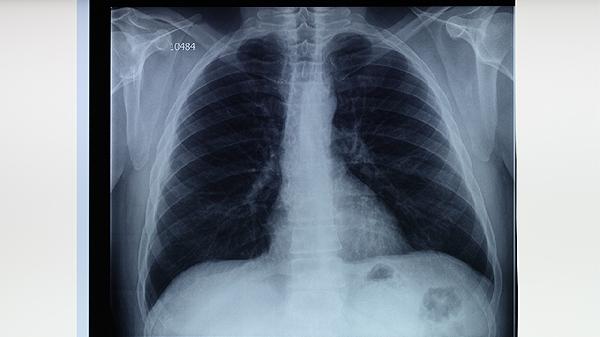

肺结核是由结核分枝杆菌引起的慢性感染,肺组织在长期炎症和感染中可能发生坏死。坏死的程度与感染的严重性、治疗是否及时以及患者的免疫状态有关。轻度坏死通常局限于小范围,而重度坏死可能涉及大面积肺组织,导致肺功能严重受损。